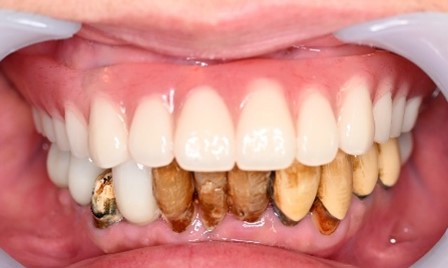

女性Iさん 60代(マグネット式入れ歯)

主訴

歯茎が腫れて、血が出ます。歯周病の治療をしてほしい。また歯をきれいにしてほしい。

治療内容

歯周病が重度に進行していました。保存することができない2本の歯を抜歯しました。歯周病の治療を徹底的にし、保存可能な9本の歯の根管治療をし、それらの歯を活用しマグネット式総入れ歯を入れました。

所感

通常の部分入れ歯にすると、入れ歯の支台になる歯は、早期に失われる可能性が高かったです。マグネット式総入れ歯は、支台になる歯に側方への力がかからないため、歯周病が進み歯の周りの骨が少なくなっている歯も効果的に活用できますし、かつ残っている歯を長持ちさせることができます。残っている歯が少なくなってきて、入れ歯で対応する場合は、マグネット式総義歯はとても良い治療法だと考えます。下顎の歯もすべて治療希望で、現在治療中です。下顎については、治療完了後に、あらためてご報告いたします。

Before

After

【義歯を装着したところ】

【義歯を外したところ】

マグネット式総入れ歯

緑丸は組み込まれたマグネット

通常の総入れ歯